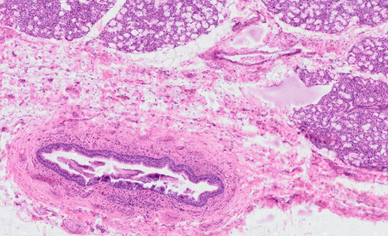

A 44-year-old man comes to the

physician because of a 6-month history of persistent cough with

yellow mucus and worsening shortness of breath. One year ago, he

had similar symptoms that lasted 4 months. He has smoked two

packs of cigarettes daily for the past 20 years.

Goblet cells and

glands typical for the respiratory tract are involved in the production of

mucus. What type of glands do we find here? (See figure)